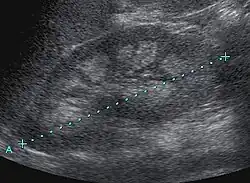

Sofern keine Nierenkoliken und keine Niereninsuffizienz vorliegen, handelt es sich oft um einen Zufallsbefund. Die Sonographie im Rahmen der Kindervorsorgeuntersuchung ist ein äußerst empfindliches Nachweisverfahren. Der Schweregrad der Veränderungen kann sonographisch unterteilt werden:[5]

- Grad I: geringe, ringförmige Echogenitätsvermehrung zwischen Markpyramiden und Nierenrinde

- Grad II: geringe diffuse Echogenitätsvermehrung der gesamten Markpyramide

- Grad III: ausgeprägte, homogene Echogenitätsvermehrung